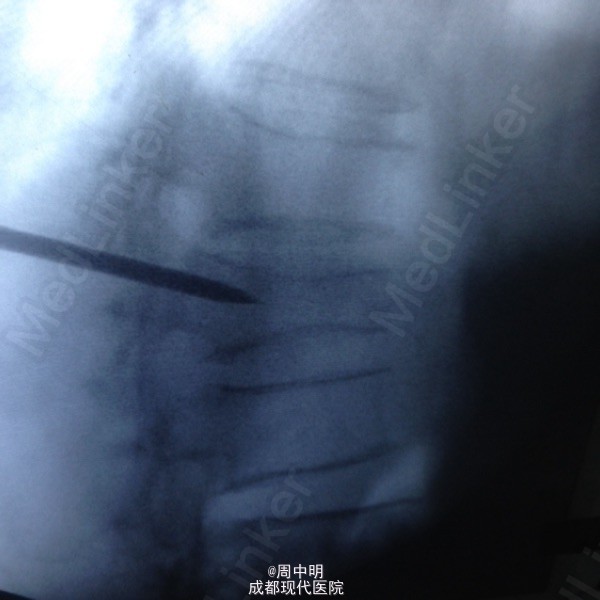

87岁,男性,T11压缩骨折

胸椎11压缩骨折